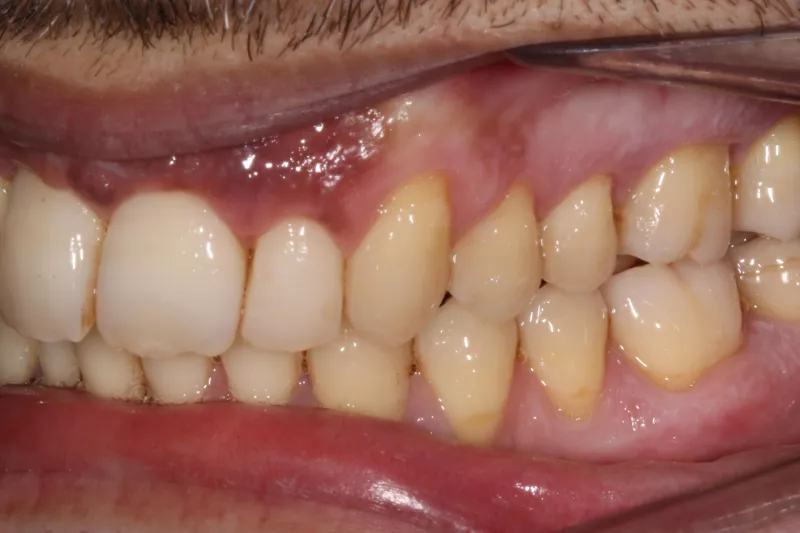

Upper Arch Invisalign to fix overcrowded teeth